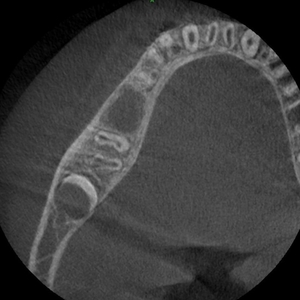

使用装置:モリタ社製ベラビューX800

2021年7月に歯科口腔外科系の撮影を行うパントモCT装置が新たに導入されました。

この装置では、2次元的に歯や顎の撮影を行うオルソパントモ撮影や顎関節撮影に加え、3次元で立体的に歯や病変を描出できるコーンビームCT撮影の機能も搭載されました。そのため従来の装置と比較して、より画質の良い、診断に有用な優れた画像検査が可能となります。

| 任意断面画像(横断像) | 任意断面画像(冠状断) | 任意断面画像(矢状断) |